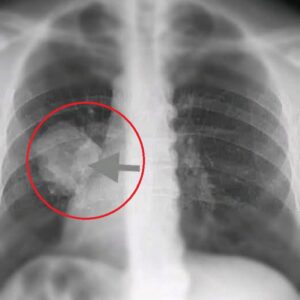

A team of researchers has reported the discovery of a possible new type of cancer that may develop silently and is difficult to detect early. Initial cases show symptoms similar to common illnesses, such as fatigue, mild fever, and digestive issues, making diagnosis more challenging.